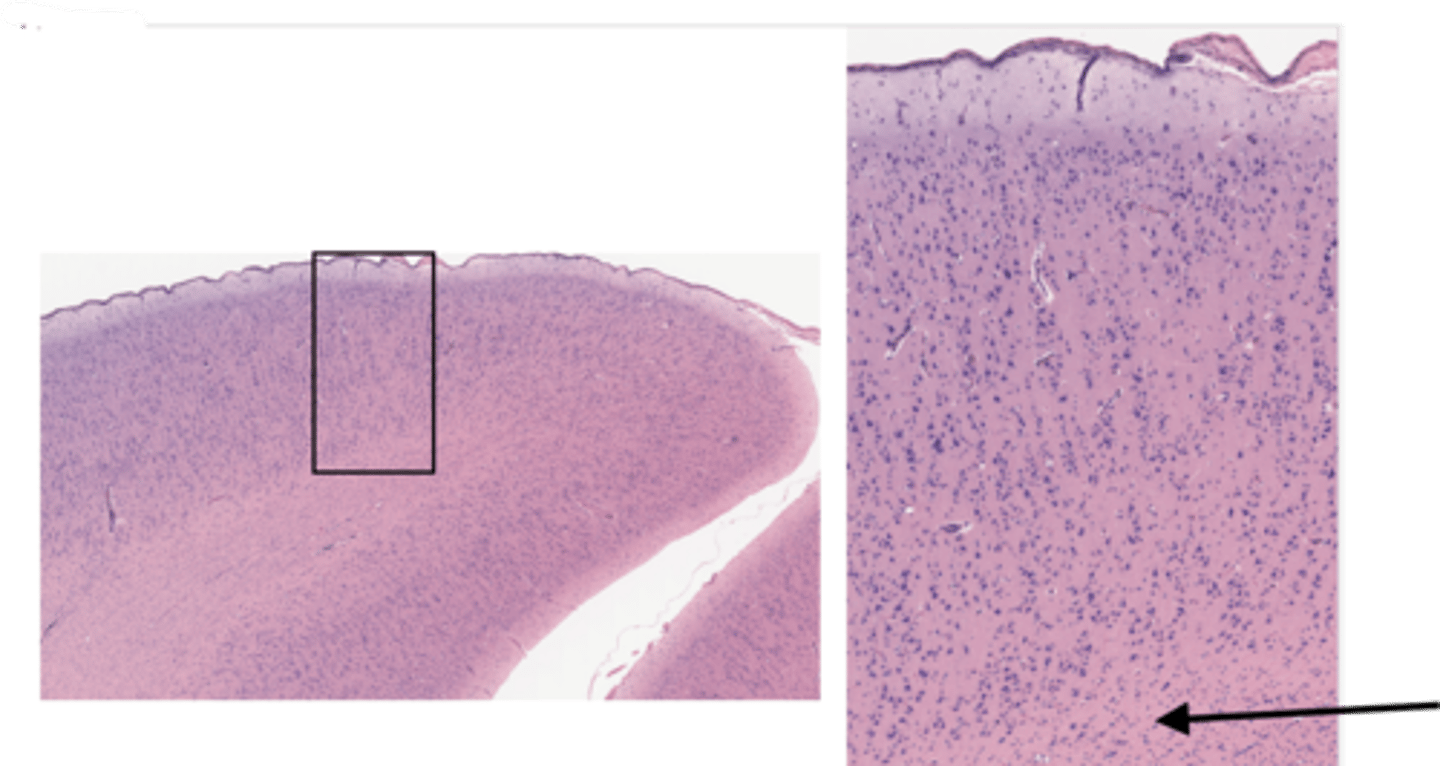

Identify the specific part of the brain

cerebrum

Identify the layer of the cerebrum

molecular layer

pia mater

arachnoid

pyramidal layer

white matter